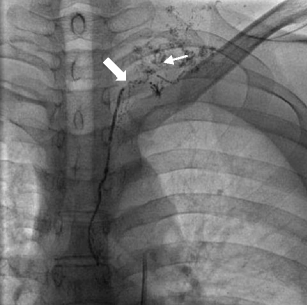

Fig. 2